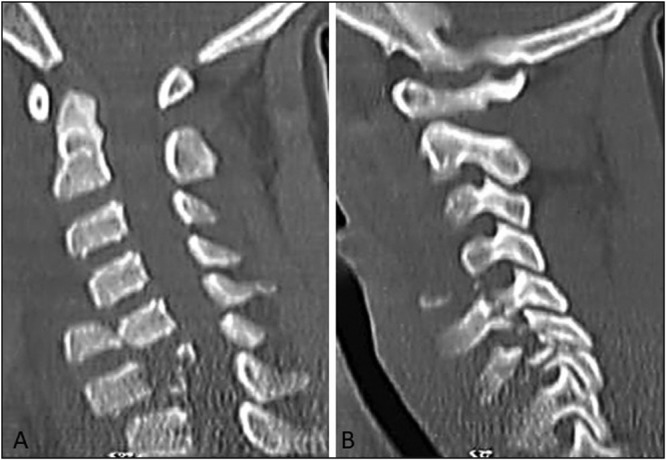

Case report: We describe a case of a 14-year-old male, who was admitted for cervicalgia with incomplete neurological deficit as a result of falling from a tree. Computed tomography (CT) of the neck revealed a posterior C5-C6 spondyloptosis with anterior spondylolisthesis of C7-T1. Surgical intervention was performed by the anterior approach only. The patient recovered completely after 2 months.